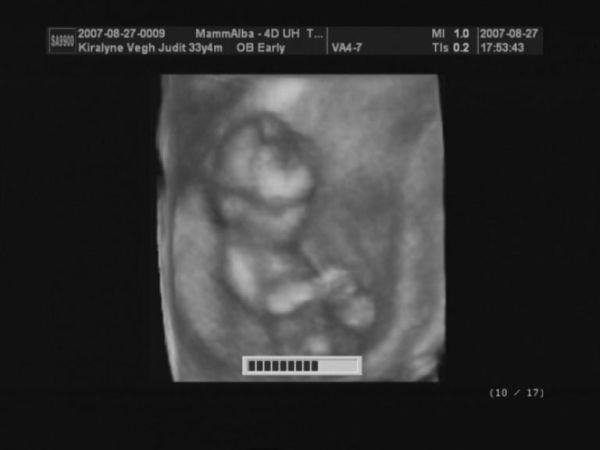

Judy, nagyon szép babátok van, gyerekek mit szóltak???